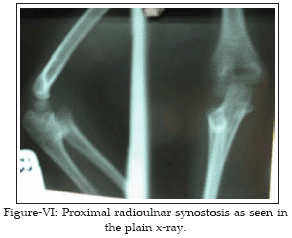

A 5-year-old daughter with right proximal radioulnar synostosis visited our clinic. She was the second child of the family. The older child did not suffer radioulnar synostosis. Her 39 year old father had suffered proximal bilateral radioulnar synostosis. Thirty years ago, when he was nine year old he visited a hospital because of limitations in supinations and fixed pronations of the two radioulnar joint. After physical and radiological examinations bilateral radioulnar synostosis was diagnosed. Surgery was recommended immediately which could not be performed due to some problems. In the physical and laboratory examination, no other anomaly was found. He actively works as a vehicle driver. He has no important problem at work. However he has fixed arm pronation and limitation in supination in both sides (Fig I-III). His daughter showed proximal right radioulnar synostosis. Laboratory and physical examinations showed no evidence of other anomaly. On physical examination, there were a fixed pronation and limited supination. Flexion and extension movements were normal (Figure IV-VI).